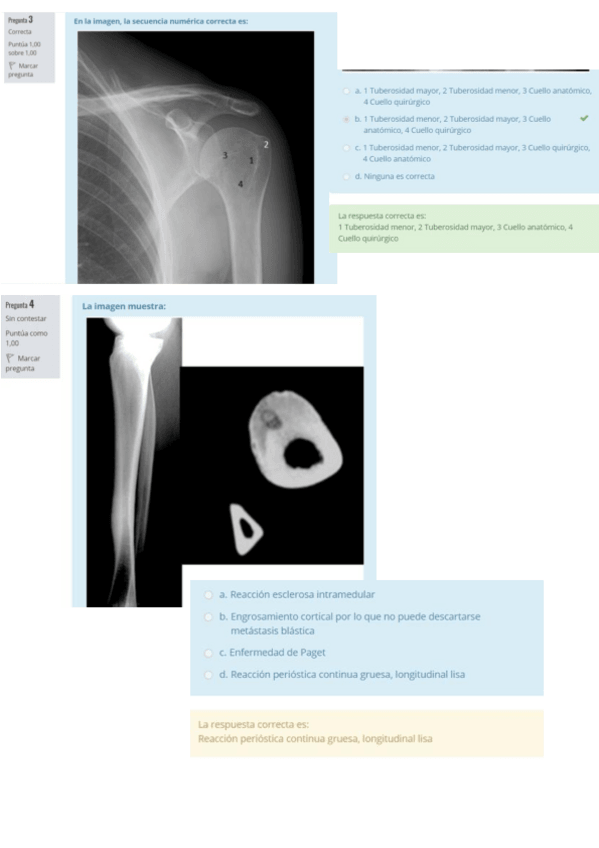

Soluciones de la 2ª práctica de musculoesquelético del curso 25-26

2 páginas